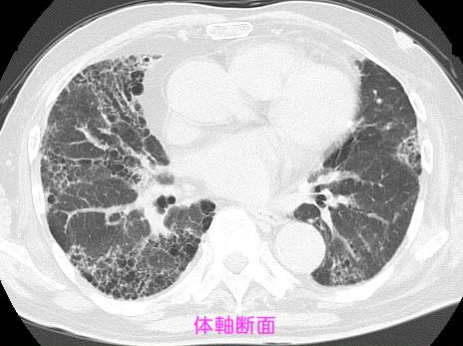

間質性肺炎とは?

肺は本来やわらかく、酸素を取り込む臓器ですが、間質性肺炎では

- 肺が硬くなる(線維化)

- 酸素を取り込みにくくなる

という変化が起きます。